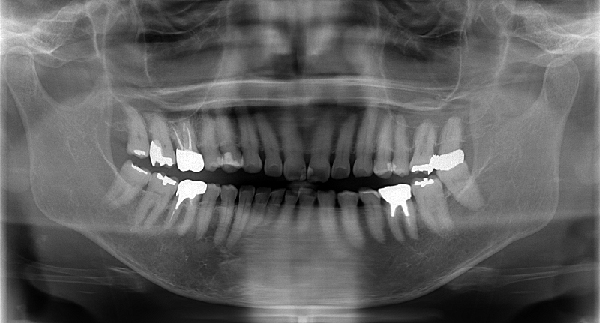

症例1

右下の奥歯の失った部位に対して、痩せた歯茎の再生治療とインプラント治療を行いました。

症例2

痩せてしまった下顎の骨を再生させる手術と歯茎を再生する手術を行い、3本のインプラント治療を行いました。